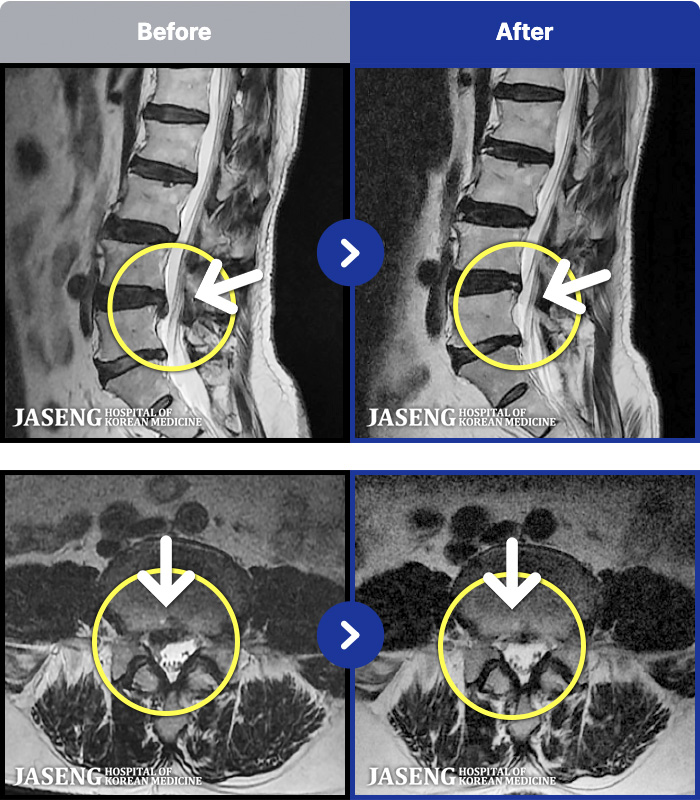

129 MRI ũ ʸ Ȯϼ.

MRI ġ

Ƹ ϰ ־.

[õ] 25.03.18~25.07.22

ȯںп Ǹ ǿ ԿǾ, ο ġ ۿ Ƿ ġḦ Ͻñ ٶϴ.